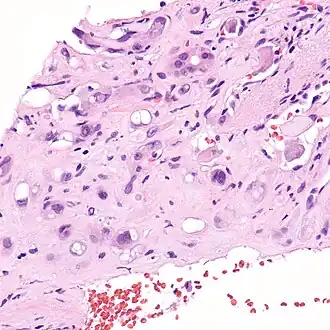

Micrografia de um hemangioendotelioma epitelióide do fígado.

Hemangioendotelioma epitelióide (HEE) é um raro tumor vascular, inicialmente descrito por Sharon Weiss e Franz Enzinger, o qual tanto clinicamente quanto histologicamente é intermediário entre o angiosarcoma e o hemangioma. No entanto, alteração genética distinta, diagnóstica da patologia, foi recentemente descrita para HEE, indicando que ele é realmente uma entidade separada tanto do angiosarcoma quanto do hemangioma.

O hemangioendotelioma epitelióide é um sarcoma de partes moles e é geralmente considerado um câncer vascular, na medida em que as  células "lesionais" expressam marcadores de superfície típicos de células endoteliais (células que revestem o interior dos vasos sanguíneos). Originalmente, foi descrito como ocorrendo mais comumente nas veias das extremidades (braços e pernas) e em dois órgãos, o fígado[1] e os pulmões. Desde então tem sido descrito em órgãos por todo o corpo. Além do fígado e dos pulmões, os ossos e a pele foram os órgãos mais freqüentes.